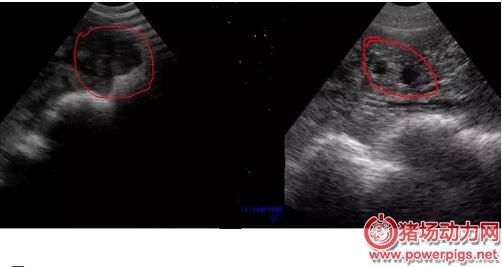

其實最好的策略是從輸精后第18天開始就用公豬來檢查母豬是否返情。隨后從第21天開始,第三周、第四周連續做兩次妊娠掃描診斷。